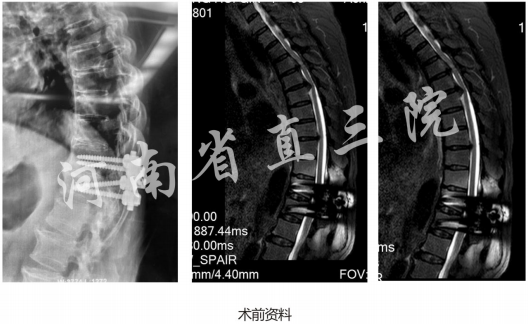

患者:张X女67岁

主诉:双下肢疼痛麻木半年,加重伴双下肢无力10天

查体:左下肢肌力肌张力0-1级,肌张力稍高,右下肢肌力1-2级,双下肢皮肤感觉均有减退,病理征阳性

入院诊断:1)T4-5/T5-6胸椎间盘突出(腹侧钙化)